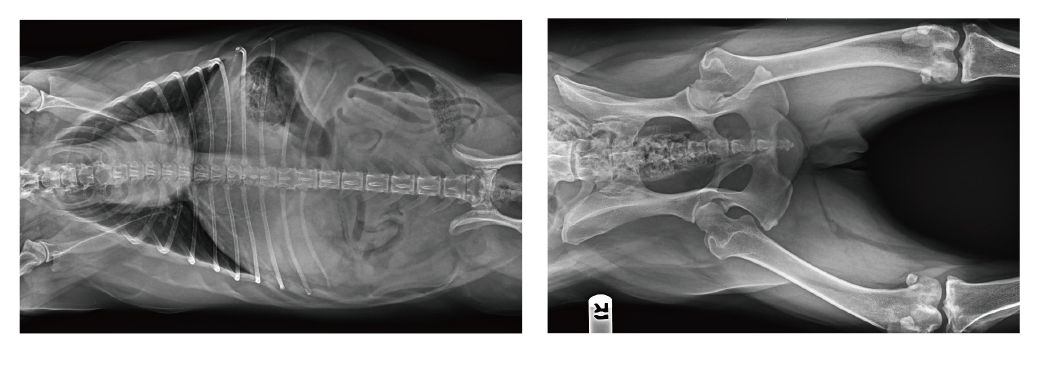

【宠物x射线机临床图像】